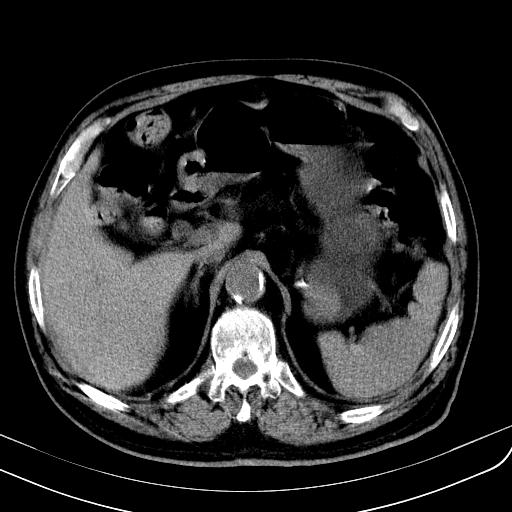

胃底靠近胃大弯处可见一圆形软组织影,直径为3.45cm,ct值约为30.1hu

胃底间质瘤

考虑为胃底间质瘤

胃底良性肿瘤,考虑间质瘤

边缘光滑,密度均匀,良性占位,首先考虑平滑肌瘤。